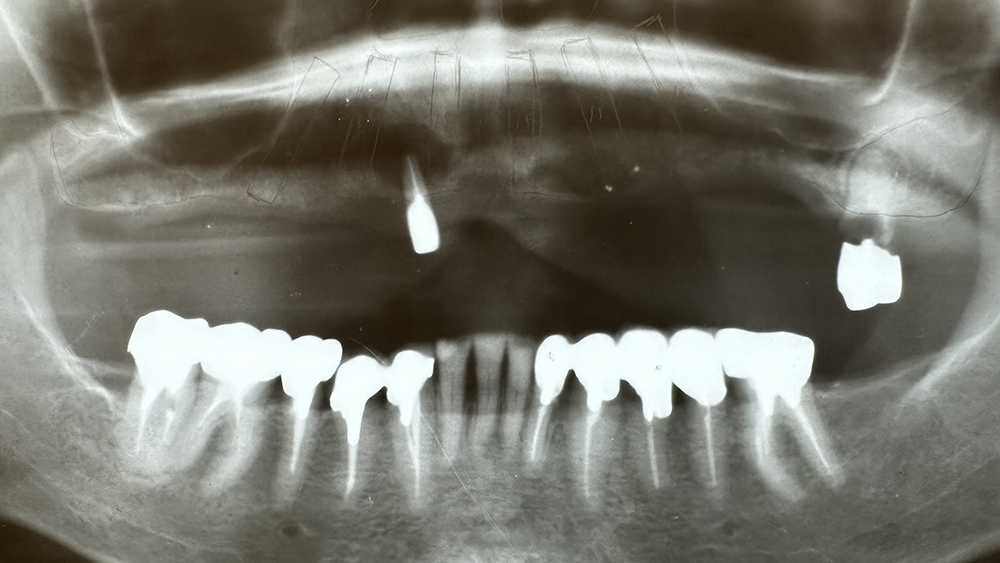

症例2

WYさん 60代女性

非喫煙者、重度歯周病

治療の期間・回数:一度目:上下とも約6か月/オールオン4:5か月

​治療の価格:一度目:上の歯1,600,000円、下の歯700,000円

オールオン4:1,600,000円

治療内容:この方は40代で重度の歯周病になり、多くの歯を失いました。

20年前に、上あごには4本のインプラントを入れましたが、骨が少なかったため、手術中に骨が割れるトラブルがありました。そのため、4か月間待ってから仮の歯を入れました。

下あごは残っている歯を使ってブリッジを作りました。最終的には上下とも、金属の土台にセラミックを貼った「メタルボンド」の歯を入れています。

その後、下あごのブリッジは10年も持ちましたが、最終的には全ての歯を失いました。そこで韓国製オステムのインプラントで「オールオン4」という方法で再建しました。手術当日に仮の歯を入れ、最終的にはスクリューで固定するメタルボンドの歯を入れています。

重度の歯周病で骨も少ない条件でしたが、上あごのインプラントは19年間安定して使えています。